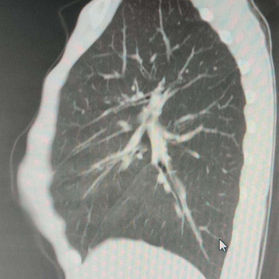

The patient's chest wall protrudes significantly, with the central part being the most pronounced and forming an acute angle deformity. Additionally, there are depressions on both sides of the lower half of the chest wall. The patient was diagnosed with severe complex chest wall deformities.